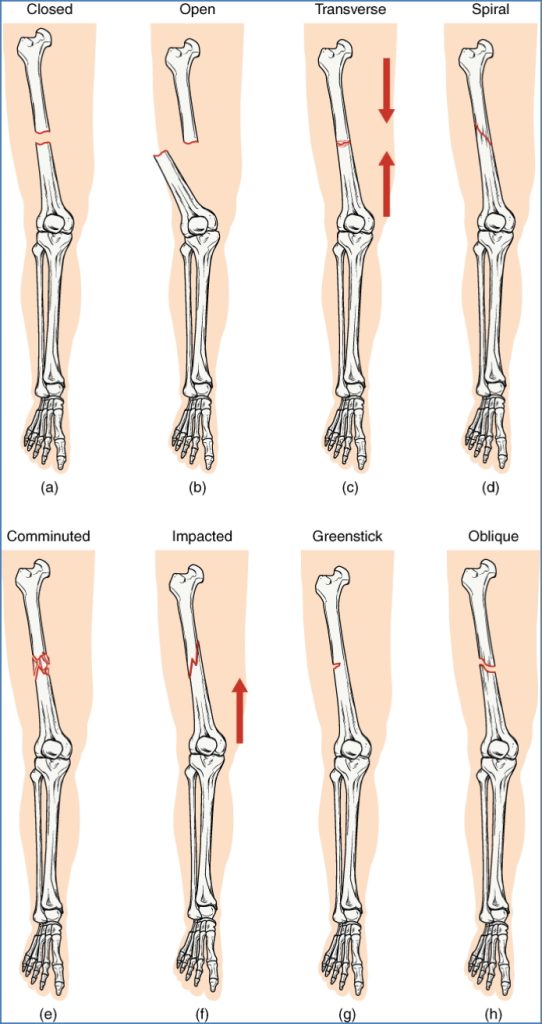

- Type of Fracture?

| Type | Description |

|---|---|

| Complete | Full separation of bone fragments |

| Incomplete | Partial separation (e.g. greenstick in children) |

| Transverse | Perpendicular to bone axis |

| Linear | Parallel to bone axis |

| Oblique | Angled across bone axis |

| Spiral | Curved pattern (often from twisting) |

| Greenstick | Partial break in flexible bone (common in children) |

| Comminuted | ≥3 bone fragments |

| Compacted | Fragments crushed into each other (common in hip) |